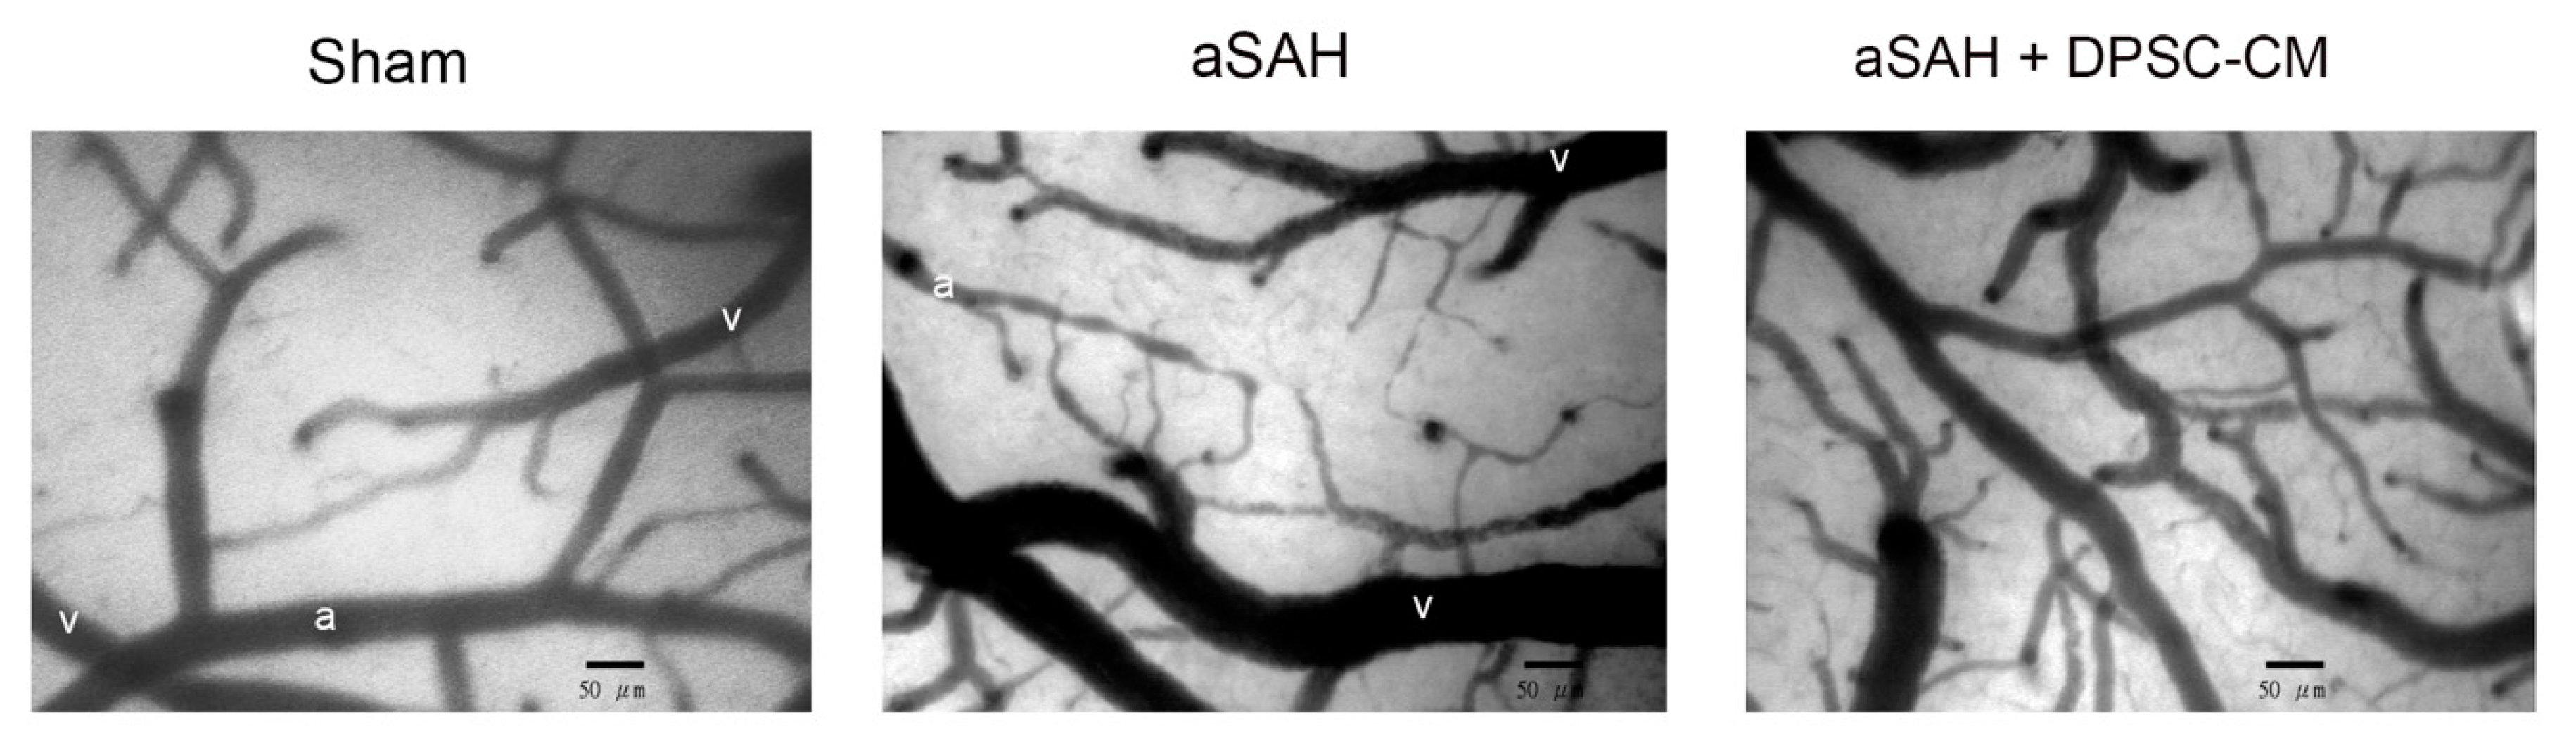

2.5. DPSC-CM Improves Microcirculation in aSAH Partially via IGF-1

4.2. Cranial Window for Observation of Microcirculation